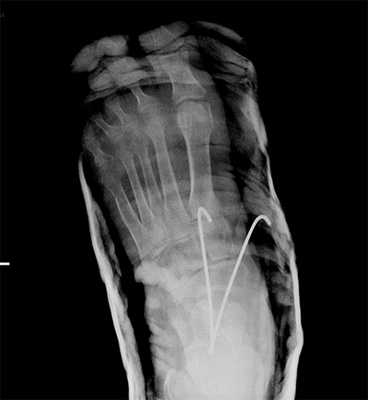

Рис. 8. Переломо-вывих в суставе Шопара

Рис. 9. Переломо-вывих в суставе Шопара

Рис. 10. Чрезкожная фиксация костей предплюсны после вправления вывиха в суставе Шопара, стопа в гипсовой лонгете